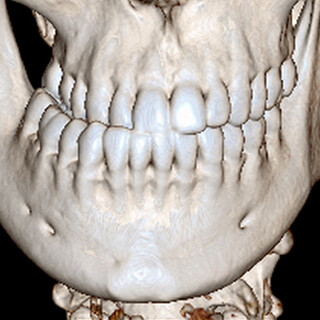

- Moderne 3D-Planungsverfahren (VSP-virtual surgical planning) und CAD/CAM Technologie

- Moderne 3D-Planungsverfahren (VSP-virtual surgical planning) und CAD/CAM-Technologie

Ein individuelles Behandlungskonzept wird in enger Absprache mit dem behandelnden Kieferorthopäden und mittels modernster digitaler 3D-Planung erstellt.

Eine gesunde Kau- und Sprechfunktion setzt einen korrekten Zusammenbiss voraus. Einfache Zahnfehlstellungen können kieferorthopädisch (mittels herausnehmbarer oder fester „Zahnspange“) korrigiert werden.

Bei sehr diskrepanter Position von Ober- und Unterkiefer zueinander kann ein funktioneller Biss jedoch oft nur chirurgisch erreicht werden. Häufig kann so auch eine Harmonisierung des Gesichtsprofils erreicht werden.